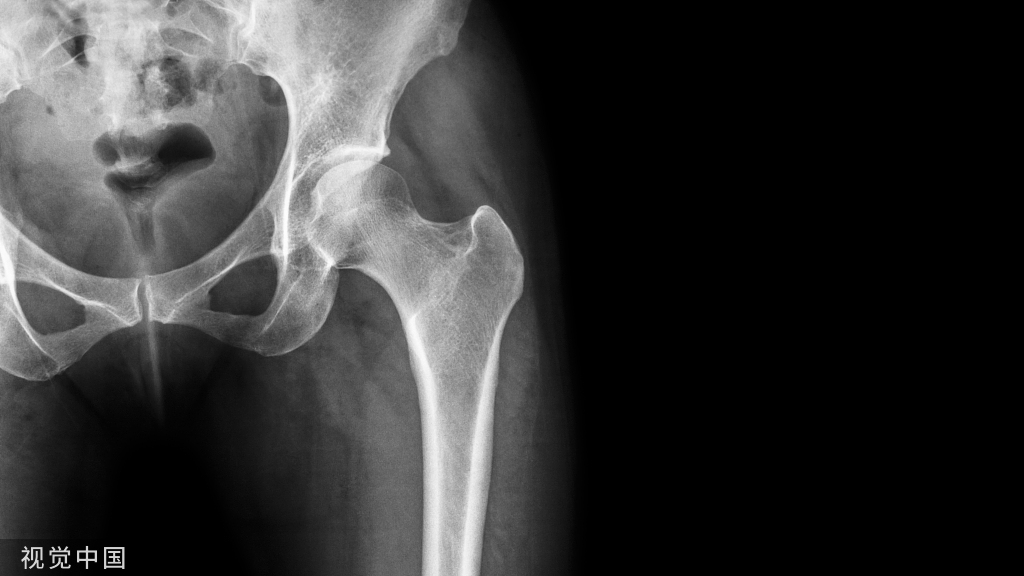

髋骨骨折主要是指髋臼骨折和股骨近端骨折,其中股骨颈骨折和股骨转子间的骨折属于最为常见的类型,约占老年人髋骨骨折的90%以上。对于老年人而言,髋骨骨折其实就意味着死亡,因为在保守治疗下,1年的生存率仅为50%。股骨颈骨折大部分是由突然跌倒或是外来暴力等原因引起的,骨折发生后,患者会出现髋部疼痛、不敢站立、患肢缩短等表现,但是也有一些在伤后仍能走路或骑自行车的情况,所以要仔细检查。